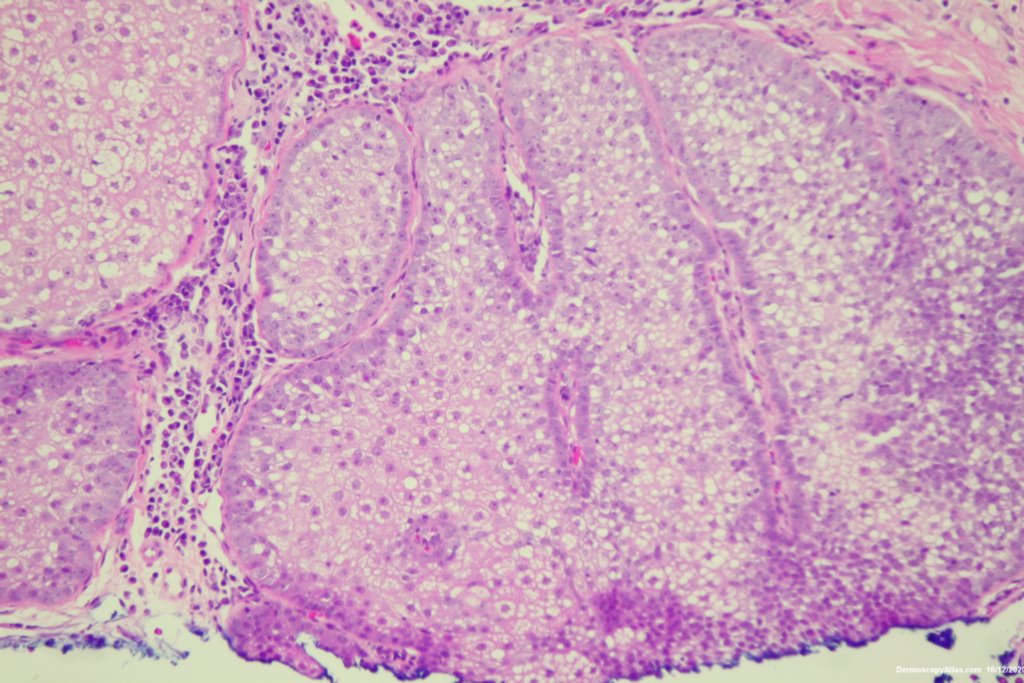

Image Number #3578 (Lentigo Maligna)

Diagnosis: Lentigo Maligna

Description: Pigmented lesion cheek and pink nodule

Elderly male with no past history of melanoma developed these two lesions over a year or so. The lentigo maligna was easy to diagnose on the clinical and dermatoscopy but the nodule was more difficult. Was it an amelanotic melanoma, BCC or SCC were the initial thoughts. Histology showed a well differentiated sebaceous carcinoma. The two lesions were excised in the same specimen with 5 mm margins. Studies failed to show the mutation for the Muir Torre syndrome which can be seen with sebaceous carcinoma.